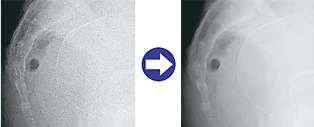

As High DQE is realized by the Fujifilm's Dual-side Reading Technology, with its low dose exposure, the FCR PROFECT CS Plus relieve patients' burden during X-ray examinations. Incorporated with the FUJIFILM proprietary image processing technology (Image IntelligenceTM), high resolution image reading with the 20 pixel/mm sampling pitch delivers excellent quality images in versatile diagnosis areas.

For example, they are suitable for diagnosis areas requiring high-quality images even with low dose exposure, such as mammography, pediatrics, follow-ups and tests using a catheter.

As an optional software specifically developed for mammographic imaging, PEM enhancement processing improves the conspicuity of micro-calcifications.